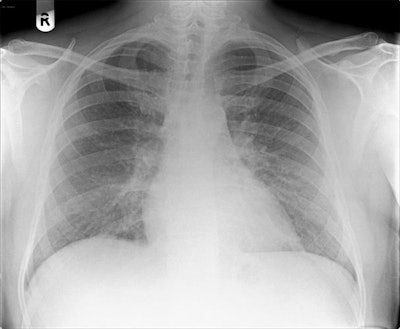

Imaging findings

"Our patient's CXR [chest x-ray] report was initially reported as normal (although we disagreed)," the authors wrote. "He subsequently had a CT pulmonary angiogram with high-resolution reconstruction (to exclude pulmonary thromboembolic as well as interstitial lung disease), reported as showing a ground glass, mosaic pattern in both lungs, with borderline enlarged hilar nodes, presumed reactive."